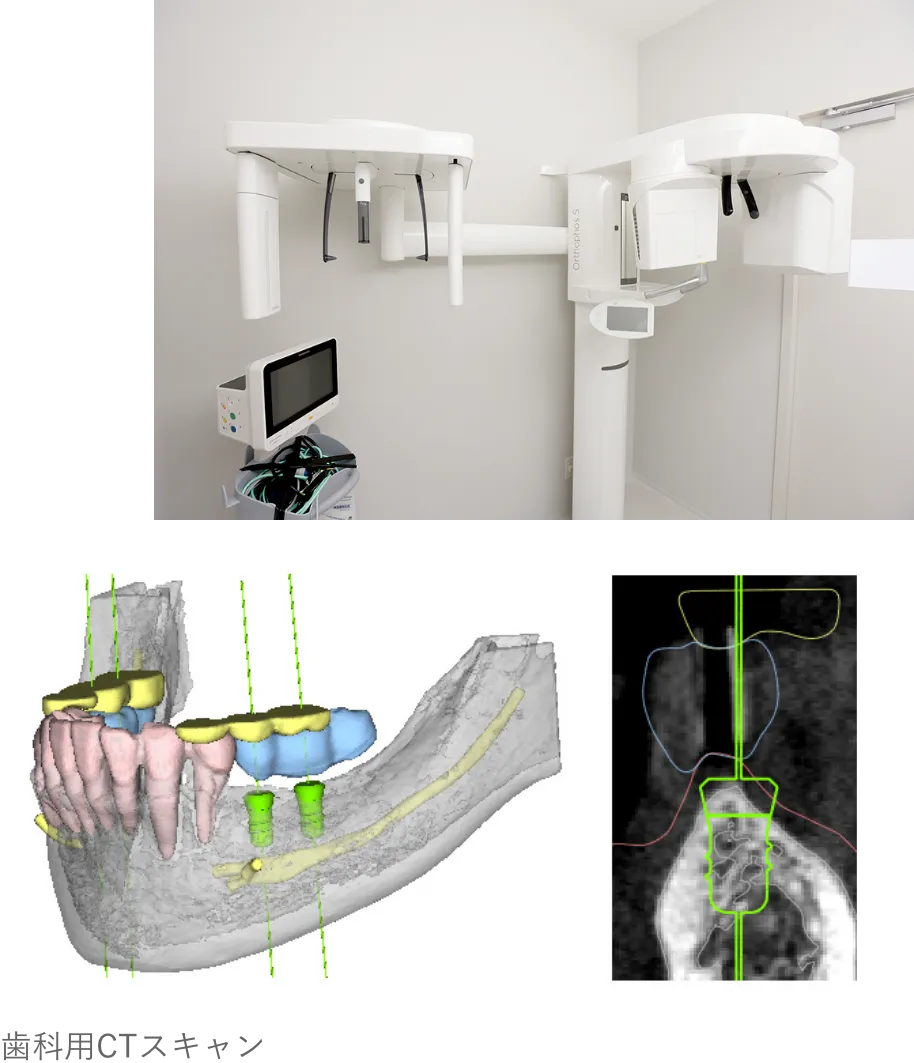

MEDICAL EQUIPMENT

CTスキャンを活用し、

患者様の口腔内を3Dモデル化

えみは総合歯科のインプラント治療は、CTスキャンで口腔内の3Dモデルを作成し、コンピュータシステム「ビオナ」を使用して歯の状態を正確に解析・診断します。

専門医とコンピュータから、精密なインプラント挿入の治療計画を作成します。機械技術と医師の腕が合わさり、患者様の手術への不安や負担を軽くして、手術(インプラント埋め込みの位置・角度)の誤差も従来のものと比べて格段に下がり、ミリ単位の誤差に抑える安全正確な手術になっています。

治療計画と

正確な

手術シミュレーションで

負担を最小限に抑えます

インプラント治療は体に負担のかかる手術を行うため、綿密な治療計画を立てた上で実行いたします。治療計画は丁寧に患者様にご説明・ご納得いただいた上で進めてまいります。

また、治療はサージカルガイドというインプラントの埋入位置の誤差をなくすためのガイドを利用します。これにより、歯ぐきを最小限もしくは全く切開せずにインプラントの埋入が可能なため手術後の腫れ、痛みが非常に少ないです。

精密検査と治療計画立案

CTスキャンで口腔内の3Dモデルを作成し、歯の状態を正確に解析・診断。精密なインプラント挿入の治療計画を作成します。

当院の対策法

当院では、インプラント手術を行う前の精密検査で通常の歯科用レントゲンだけでなく、CTスキャンの骨の情報とお口の型取りによる歯肉の粘膜の情報をコンピュータ上で統括してシュミレーションを行うことで加えて骨の内部の神経の走行を把握した上で、安全に治療を行なっていますのでご安心ください。

当院の対策法

こちらに関しても、CTスキャンによるシュミレーションを行い位置の把握ができますので、当院ではこのようなことが起こることはありません。

当院の対策法

こちらに関しても、CTスキャンによるシュミレーションを行い位置の把握ができますので、当院ではこのようなことが起こることはありません。